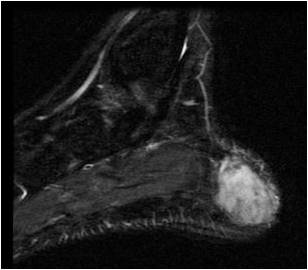

Fig. 3 & 4: MRI Sagittal (Fig. 3) and Coronal (Fig. 4) T2 weighted images of the right foot show a well-circumscribed soft tissue mass with high signal intensity admixed with some hypointense areas, located along the posterior and medial aspect of the calcaneous bone.